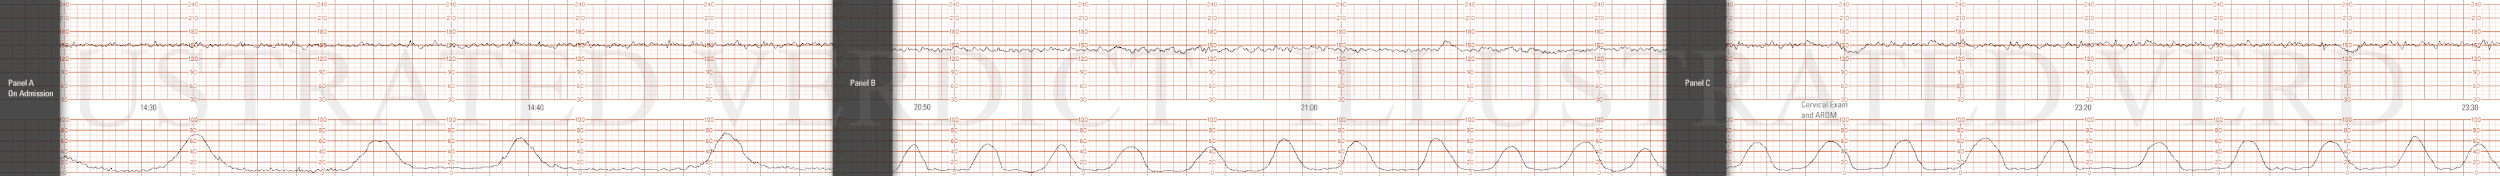

STRIP 76

1. Ctxs – 11 contractions each 50 sec 55 sec 50 sec, etc duration (3rd contraction from end too long)

Baseline -140bpm with mod variability -7-8 bpm

Decels - None

Accels – None until scalp stimulation to be written on strip done at 14 min into strip – 18 bpm x 20 sec

Ctxs2 – 10 contractions – each 60, 65, 60, 65 etc sec duration.

Baseline2 – 150 bpm with mod variability 7-8 bpm

Decels2 - Late Decel with Ctx 2, Ctx 8 (more gradual, less variable looking), each 15 bpm nadir

Variability2 – moderate at 7-8 bpm

Accels2 – none scalp stim not done.